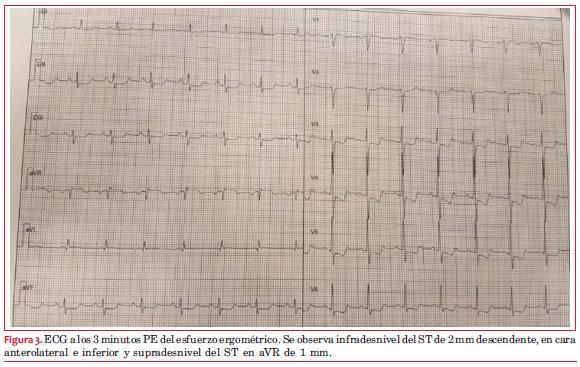

Ante el resultado de la PEG se decide realizar centellograma de perfusión miocárdica MIBI sensibilizado con esfuerzo ergométrico. El ECG basal del estudio muestra una repolarización ventricular normal. El ECG al máximo esfuerzo (

Test presor normal. El paciente no presentó ángor. Al máximo esfuerzo se inyectó el radiofármaco y a los 60 minutos se obtuvieron las imágenes posesfuerzo. A las 24 horas se reitera el estudio en condiciones basales. Se observa captación uniforme del radiofármaco en el VI, tanto en reposo como en esfuerzo. No hay evidencia centellográfica de isquemia. La FEVI en reposo fue de 61% y en luego del esfuerzo de 67%.